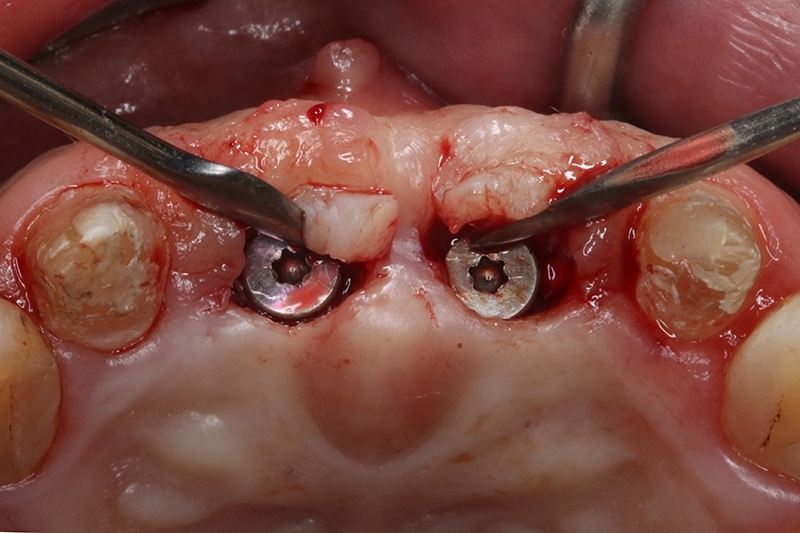

可見植體移除後骨缺損範圍大

植體植入,置放於理想的水平與垂至高度位置